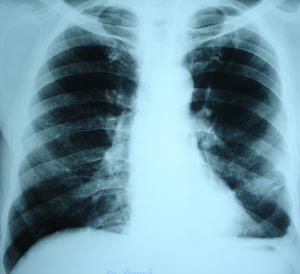

The thickened pleura casting an uniform shadow masking the real position of diaphragm .Flattening of left dome of diaphragm. This can be seen as a residual effect of pleural pathology.